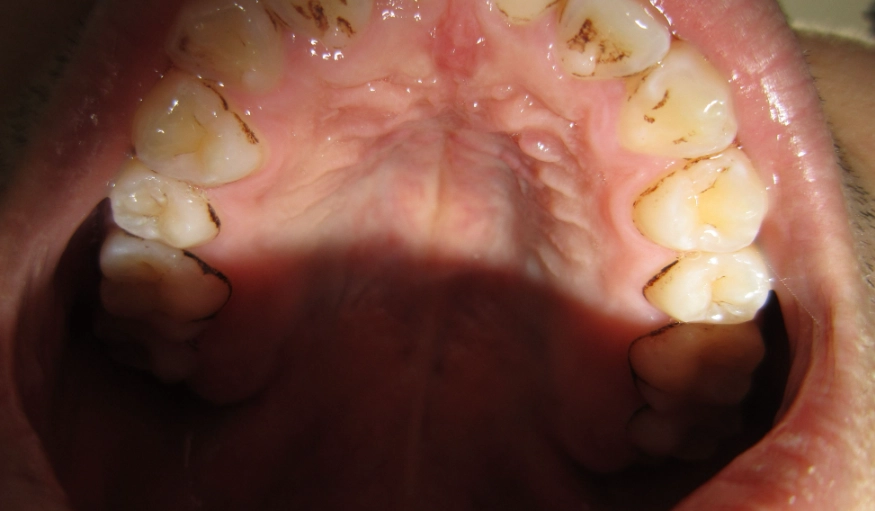

第一步:先對號入座!7種常見腫脹原因圖文對照

原因沒搞清楚,所有處理都是白費力氣。牙齒後方腫脹,九成離不開下面這七種狀況。你可以先對著鏡子,看看自己的情況比較像哪一種。

| 1. 智齒冠周炎 | 腫脹集中在最後一顆牙(智齒)的牙齦瓣上,可能覆蓋部分牙冠。按壓有膿或血水滲出,伴隨劇烈抽痛、張口困難。 | 20-35歲年輕族群最常見。飯後食物殘渣卡進智齒與牙齦的縫隙,清潔不到而引發感染。 | 高(易惡化) |